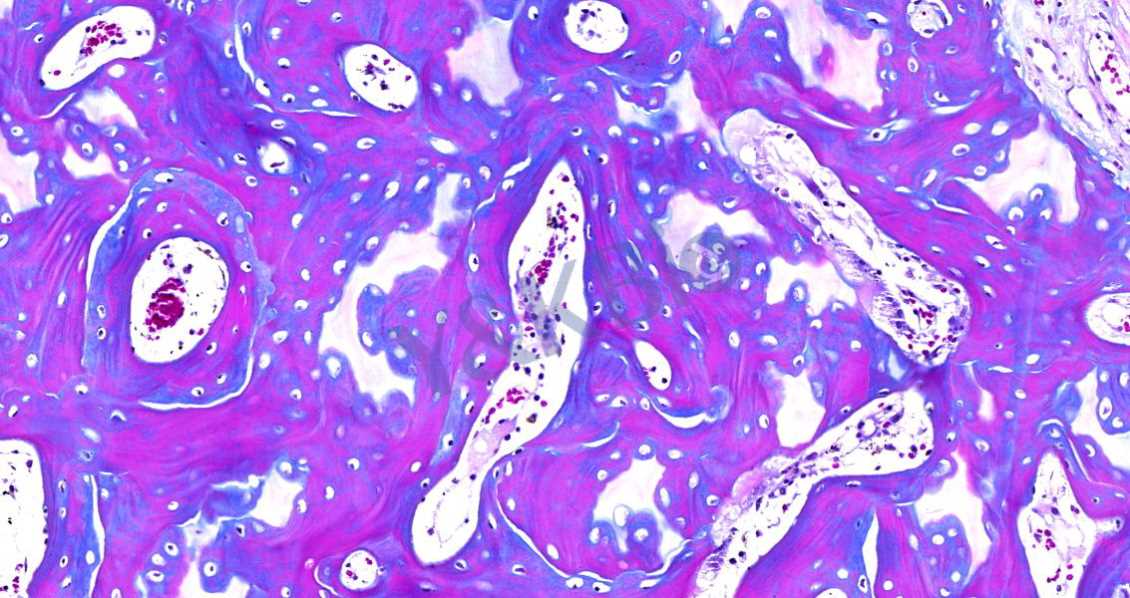

Masson染色的颜色对比鲜明,可见明显的胶原纤维网(甘肃苯胺蓝染色则为蓝色,甲基绿则为绿色),能较好地反映纤维组织的形态。其中,蓝色表示新形成的骨,红色表示成熟的骨组织。

3.番红O-固绿染色

番红O-固绿染色可直观反映关节软骨、软骨下的骨组织结构,嗜碱性的软骨与碱性染料番红 O 结合呈现红色,嗜酸性的骨和酸性染料固绿结合而成蓝色,在关节软骨及软骨下骨的形态学研究中受到了欢迎。